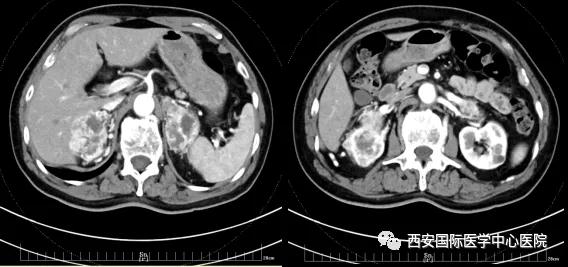

今年七十五歲的患者,來自陜西省商洛市,四月前因腰背部疼痛就診于當?shù)蒯t(yī)院,行CT檢查發(fā)現(xiàn)“右腎、雙側腎上腺占位,前縱膈淋巴結腫大,雙肺多發(fā)結節(jié)、胸椎骨質破壞,考慮轉移瘤”。為進一步診斷治療,患者的兒子帶他來到西安某三甲醫(yī)院,查泌尿系CT提示“右腎占位性病變,多考慮腎癌,雙側腎上腺多發(fā)轉移灶,腹膜后多發(fā)腫大淋巴結”;行穿刺活檢提示“腎透明細胞癌”;并給予患者口服靶向藥物的治療方案。

自四月份至今,患者一直口服靶向藥物治療(阿昔替尼5mg 2次/日),期間無不良反應,目前腰背部疼痛癥狀也有所緩解,復查影像學資料提示瘤體較前縮小,腫瘤完整切除的可能性明顯提高;而且患者的兒子也是一名外科醫(yī)生,所以他更想為父親完成后續(xù)的手術治療。

患者一家慕名前來到西安國際醫(yī)學中心醫(yī)院找到楊增悅教授。楊增悅教授仔細看完患者的之前的影像學及病理資料后,診斷為:右腎透明細胞癌(T4N1M1);并安排他住院。而后,主管醫(yī)生及時為他完善了術前檢查及評估。7月15日,在麻醉手術中心柴偉主任、王彬榮副主任、李娟護士長、李瑞剛護士長及全體麻醉手術中心團隊的有力保障下,成功完成了這臺“大”手術。

手術由楊增悅教授主持,舒濤主治醫(yī)師、王東主治醫(yī)師主刀,黃怡醫(yī)師、王平醫(yī)師協(xié)助完成。由于第四代達芬奇機器人更加靈活和精準的特性,手術全程順利,尤其是完全精準的“解鎖”了右腎動脈和右腎靜脈的數(shù)十根交互纏繞的分支血管。術后患者麻醉恢復后生命體征平穩(wěn),順利返回泌尿外科普通病區(qū)進一步康復。